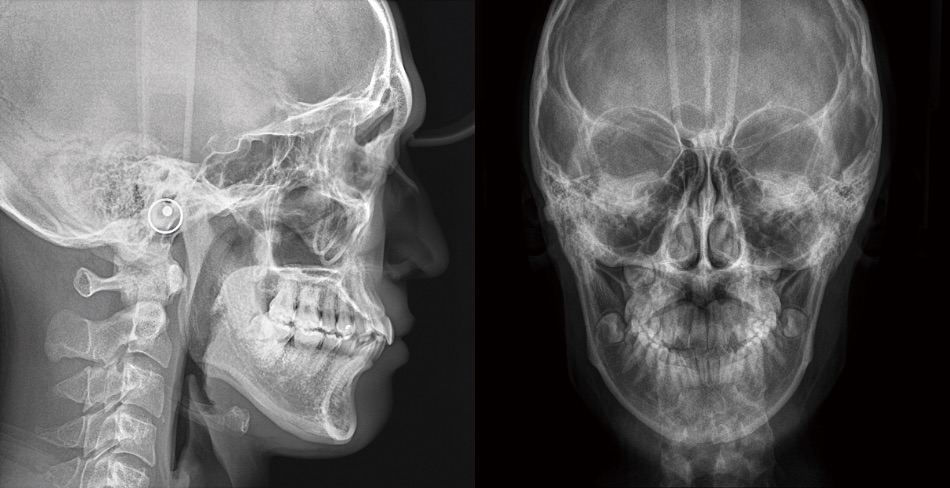

セファロ側方撮影

セファロAP方向撮影

ウォーターズ法撮影

頭部一軸方向撮影